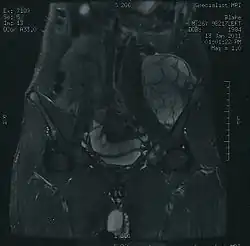

Imaging studies – including radiographs ("x-rays"), computerized tomography (CT), and magnetic resonance imaging (MRI) – are often used to make a presumptive diagnosis of chondrosarcoma.[9] However, a definitive diagnosis depends on the identification of malignant cancer cells producing cartilage in a biopsy specimen that has been examined by a pathologist. In a few cases, usually of highly anaplastic tumors, immunohistochemistry (IHC) is required.

There are no blood tests currently available to enable an oncologist to render a diagnosis of chondrosarcoma. The most characteristic imaging findings are usually obtained with CT.[10]